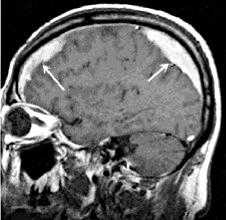

КТ головного мозга. Геморрагический инсульт, обширная интрапаренхиматозная гематома в левой гемисфере

Они позволяют определить объем и локализацию внутримозговой гематомы, степень дислокации мозга и сопутствующего отека, наличие и область распространения кровоизлияния. Желательно проведение повторных КТ-исследований, чтобы проследить эволюцию гематомы и состояние мозговой ткани в динамике.